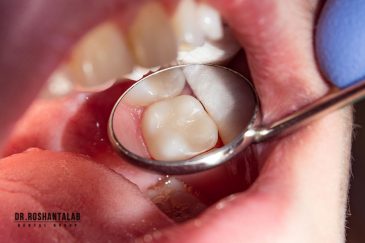

طراحی لبخند هالیوودی با متدهای لمینت سرامیکی دندان و کامپوزیت ونیر در کنار اصلاح فرم، خدمات بلیچینگ و روکش دندان، زیبایی چهره شما را تکمیل میکند.ترمیم دندان

از عصب کشی و درمان ریشه دندان گرفته تا جراحی لثه و کشیدن دندان، تمامی مراحل توسط متخصص ترمیم دندان مدیریت میشود. ارائه باکیفیتترین خدمات ترمیم دندان برای سلامتی شماست.کاشت ایمپلنت فوری دندان